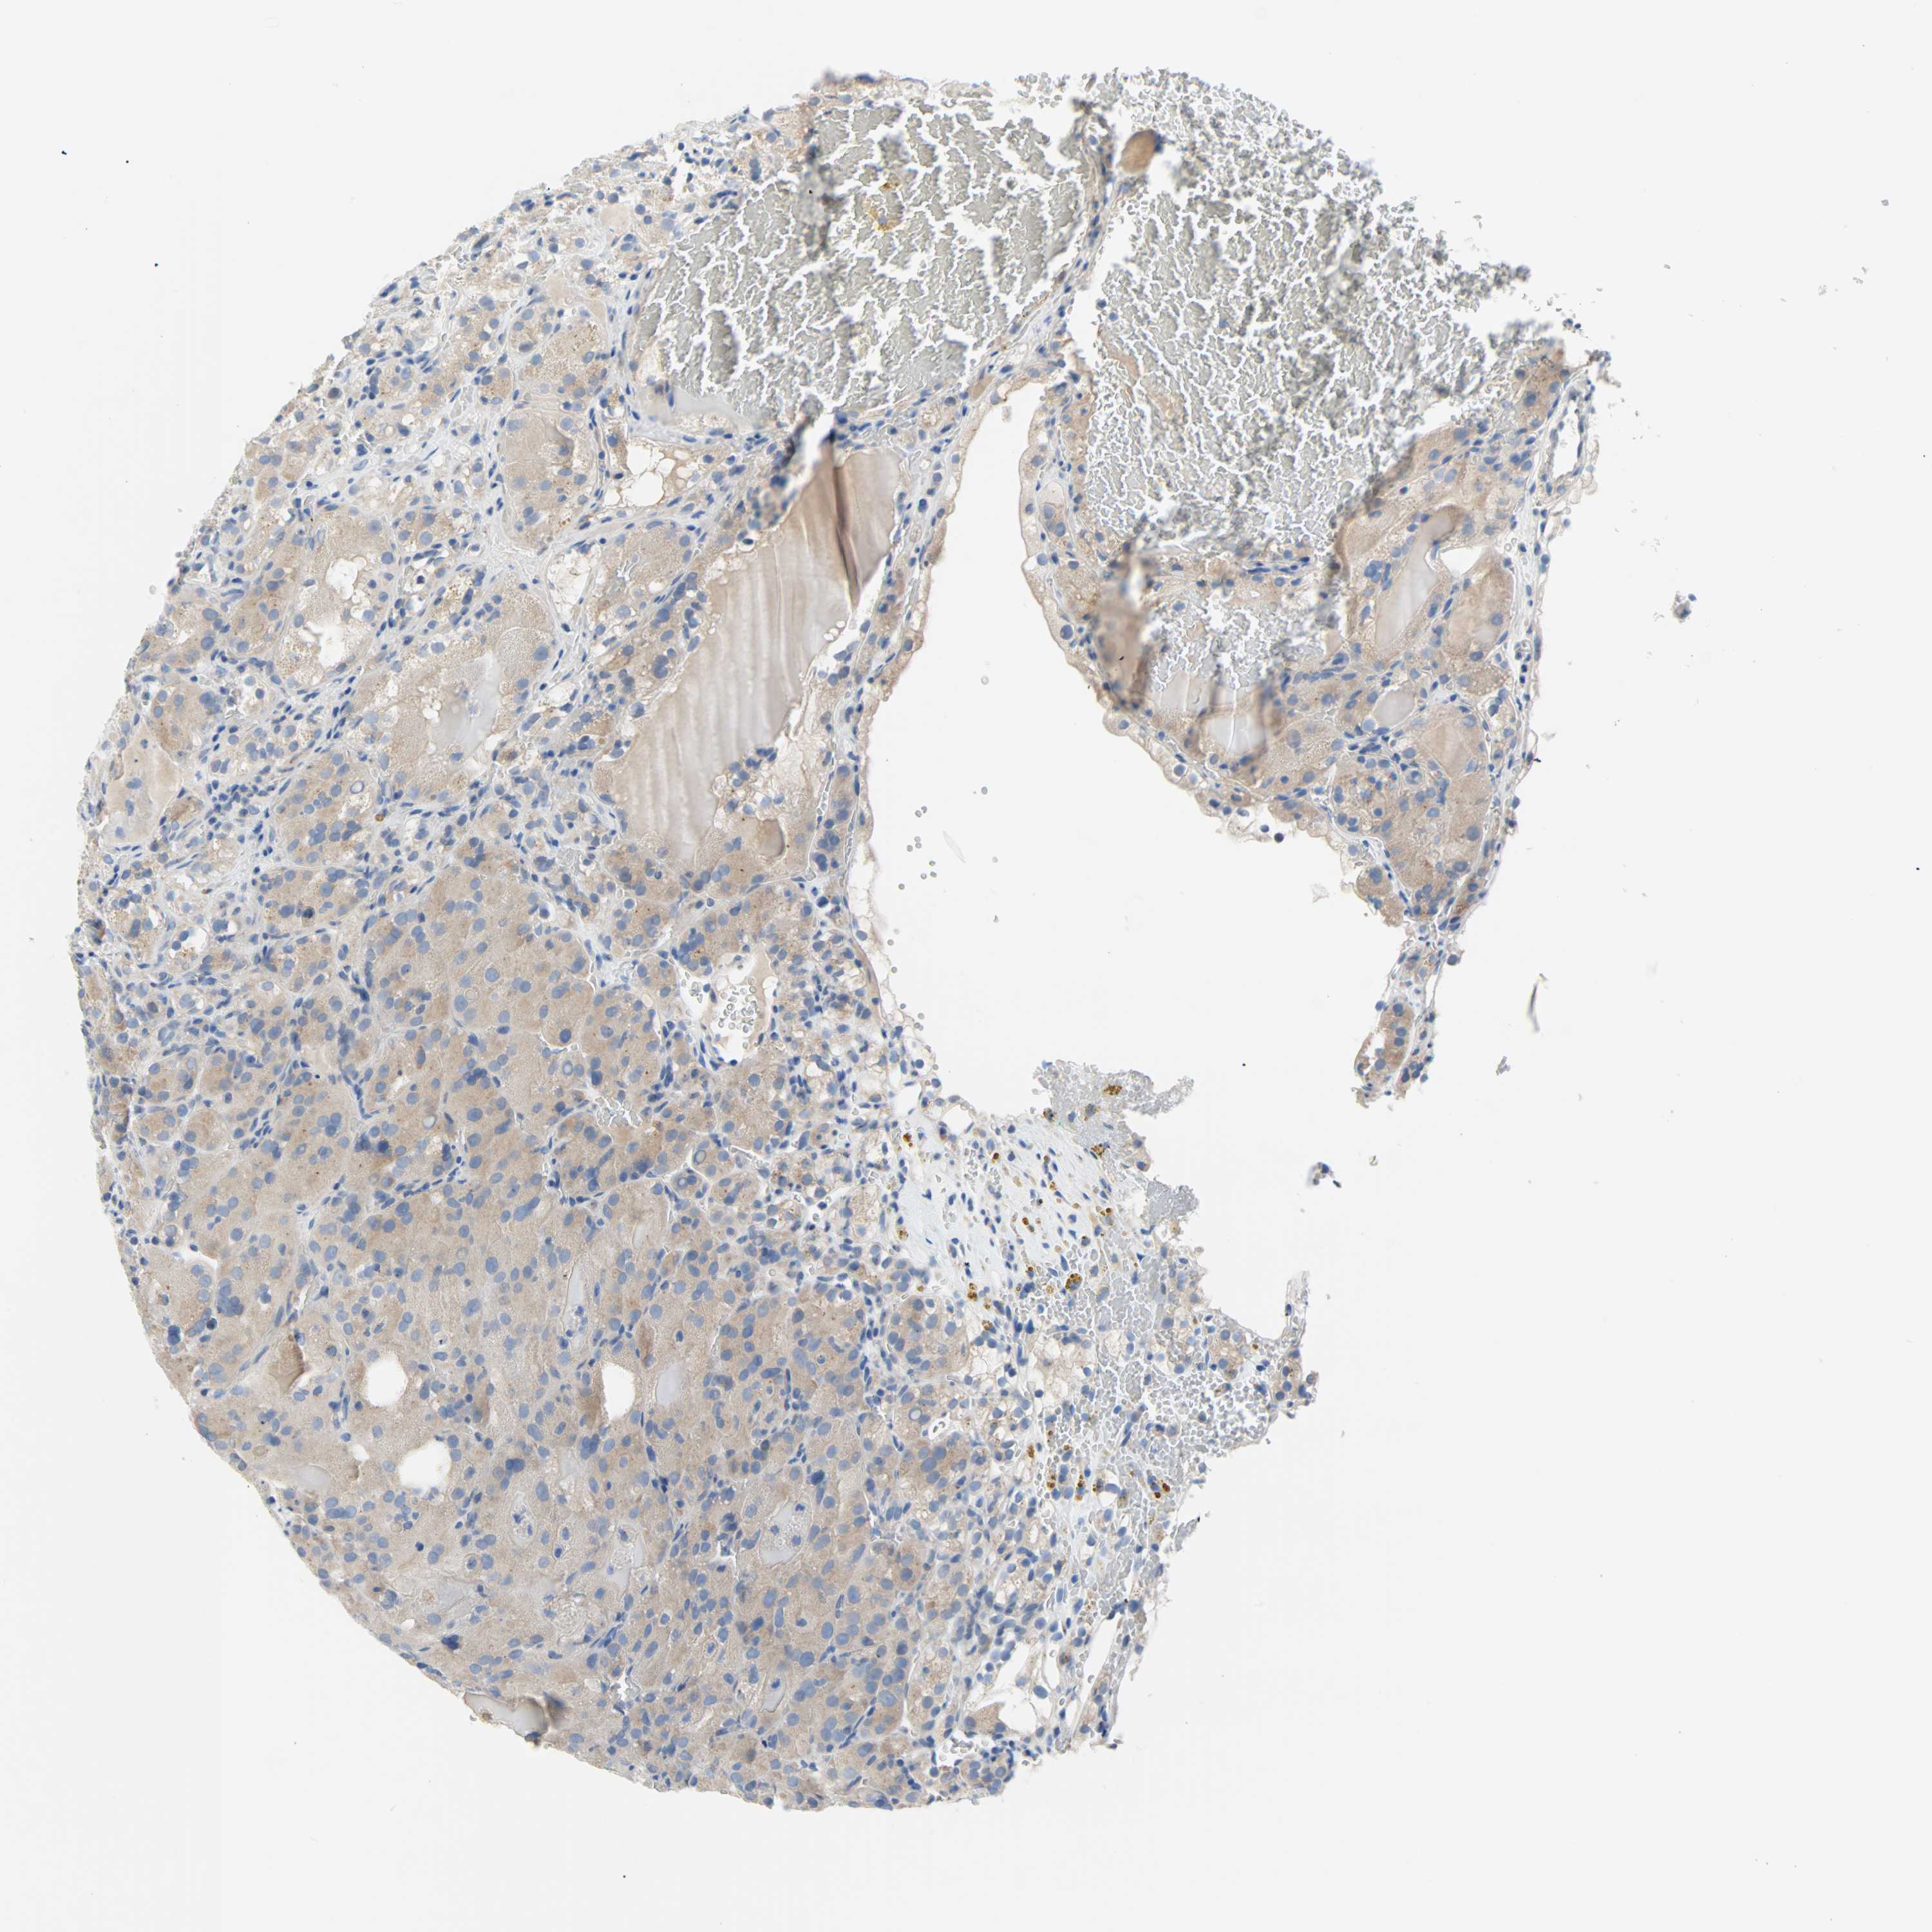

Average pTPM 3.2

Number of samples 100